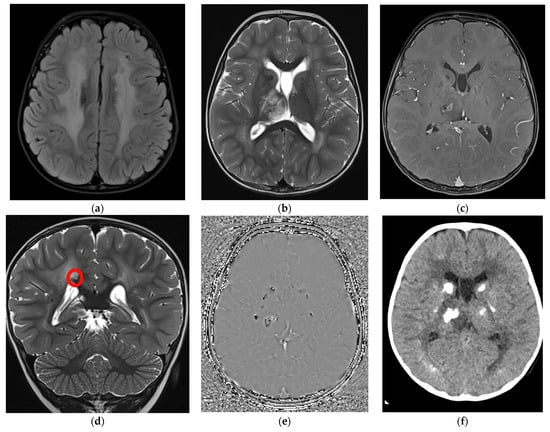

Considering the persistence of pathological signs on cuS, a brain MRI was performed at two months and three weeks of corrected age (CA), showing a hypointense nodular alteration through gradient echo weighted images (Figure 1).

At two years and three months of age, mild neuropsychomotor delay was confirmed through the Griffiths Scale of Child Development 3rd edition (developmental quotient was 70, at the 2nd percentile) with greater impairment in expressive language (language and communication quotient 65 that is under the 1st percentile). At the same age, the head circumference settled at the 50th percentile. Visual and auditory evoked potentials, abdominal ultrasound, ophthalmological examination, and biochemical and metabolic blood assessment were within normal limits. Electroencephalogram in partial sleep deprivation disclosed nonspecific abnormalities (slow and sharp activity in bilateral fronto-central regions) without clinical correlates. Brain MRI scans (Figure 2a–e) documented signs of diffuse leukoencephalopathy with symmetrical white matter involvement with sparing of the corpus callosum and “U” fibers. This finding came with punctate to nodular alterations, confirmed to be calcifications at the subsequent CT scan (Figure 2f), which were predominantly located at the level of the basal nuclei and thalami, cortico-subcortical, and periventricular areas. A one-centimeter cyst was found at the level of the splenium of the corpus callosum.

Evidence of a focal edematous alteration demarcated by contrast enhancement and containing a poorly defined calcification was noted in the right thalamus; this latter image was interpreted as the site of probable future cystic degeneration. The interferon signature result was negative. These elements, associated with the specificity of the neuroradiological features (diffuse leukoencephalopathy with symmetrical white matter involvement, presence of the small intracerebral cyst associated with the right thalamic lesion with a likely cystic evolution and bilateral calcification) and the significant discrepancy between the latter and the mild child’s neurological picture suggested the hypothesis of LCC. Two pathogenic variants in SNORD118, n.59T > C and n.*5C > G, were detected at Sanger sequencing, and consequently, the diagnosis of LCC was confirmed.

Figure 2. Brain MRI at 2 years and 3 months with axial Flair (a), axial (b), and coronal (d) T2-TSE, axial T1-Tse post gadolinium (c), phase image of the susceptibility weighted imaging (SWI) (e), and axial CT without contrast (f). (a) a diffuse white matter hyperintensity is evident in both hemispheres; (b,c) a right thalamic involvement is also evident with central and not homogeneous contrast enhancement after gadolinium injection; (d) a small millimetric cyst (red circle) can be detected over the right portion of the splenium of the corpus callosum, hyperintense on T2; (e) diffuse calcification are documented as hypointense foci on SWI (e) and hyperdense on CT (f) in both basal ganglia, thalami were they appear as rock lesions and juxtacortical, where they are more punctate or linear.